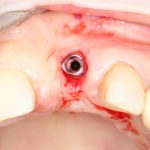

Рекомендации по установке имплантов. Для всех. Часть V.